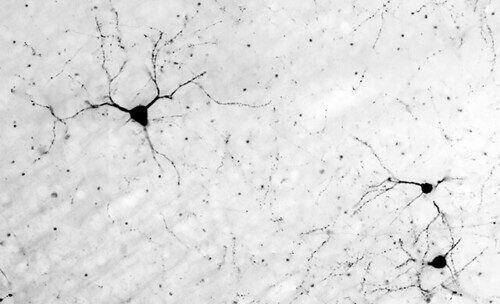

Svarbus mikroglijų vaidmuo: mokslininkai paaiškino, kodėl su amžiumi silpnėja smegenų ryšiai

Naujas tyrimas rodo, kad senstant smegenų „šiukšlių šalinimo“ sistema ima veikti prasčiau: ilgaamžės nervinės ląstelės (neuronai) pradeda perduoti sulipusius, pasenusius baltymus kitoms smegenų ląstelėms.

Daugelis šių baltymų dalyvauja signalų perdavime sinapsėse – smulkiose jungtyse tarp neuronų. Tačiau su amžiumi baltymai nebe taip lengvai suskaidomi, ima kauptis ir tarsi „užkemša“ sinapses, trukdydami jų darbui.

Tuomet į pagalbą ateina atraminės smegenų ląstelės – mikroglijos. Jos pašalina užsikimšusias sinapses, kad neuronai ir toliau galėtų perduoti signalus. Vis dėlto, tyrėjų teigimu, toks valymas ilgainiui gali sutrikdyti smegenų ląstelių tarpusavio ryšius.